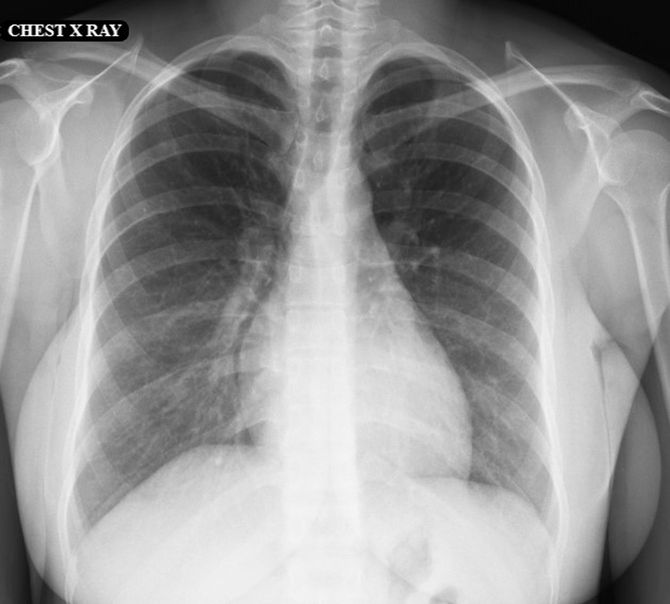

近所の病院を受診したが治らず、8月末に市内の大きな病院で内臓のCTを撮ることに。

9月に結果を聞きに行くと、「前縦隔(縦隔:胸の中心にある左右の肺の間にある空間)に腫瘍性病変の疑いがあり」と言われ、専門の病院を紹介される。

紹介された大学病院へ行くと、「重症筋無力症」と診断。治療のために10月に入院し、11月には胸腺腫(リンパ球を作っている胸腺の腫瘍)の手術を受けた。胸腺腫は悪性腫瘍でステージII。主治医は「手術で見える範囲は取り除いた」と説明した。